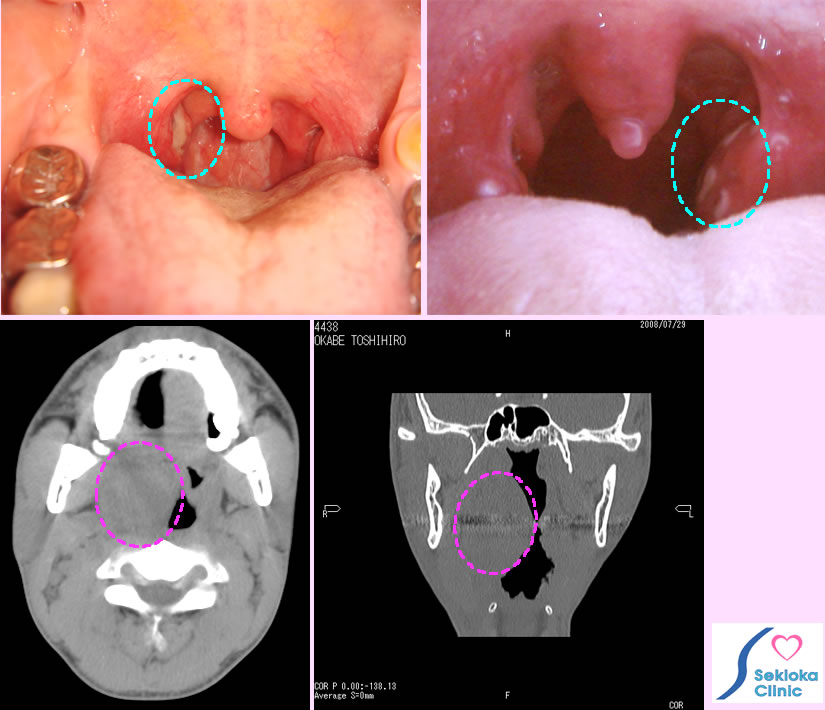

扁桃腺炎

喉の痛み、熱。時に風邪と思って受診される方もあります。治療が遅れると感染は扁桃周囲膿瘍にまで進展し、嚥下障害(食事を飲み込めない)、開口障害も出現することがあります。

診断

視診でほぼ診断される。扁桃腺表面から細菌検査を行うが多くは結果を待たず抗生剤を開始。扁桃腺周囲に広がっている疑いがある場合、開口障害がある場合は 造影CTなどで周囲膿瘍を診断します。

治療

抗生剤の服用、重症では点滴。他に去痰剤、抗炎症剤の併用。扁桃周囲膿瘍が広がる場合は 切開、ドレナージで膿を排出。